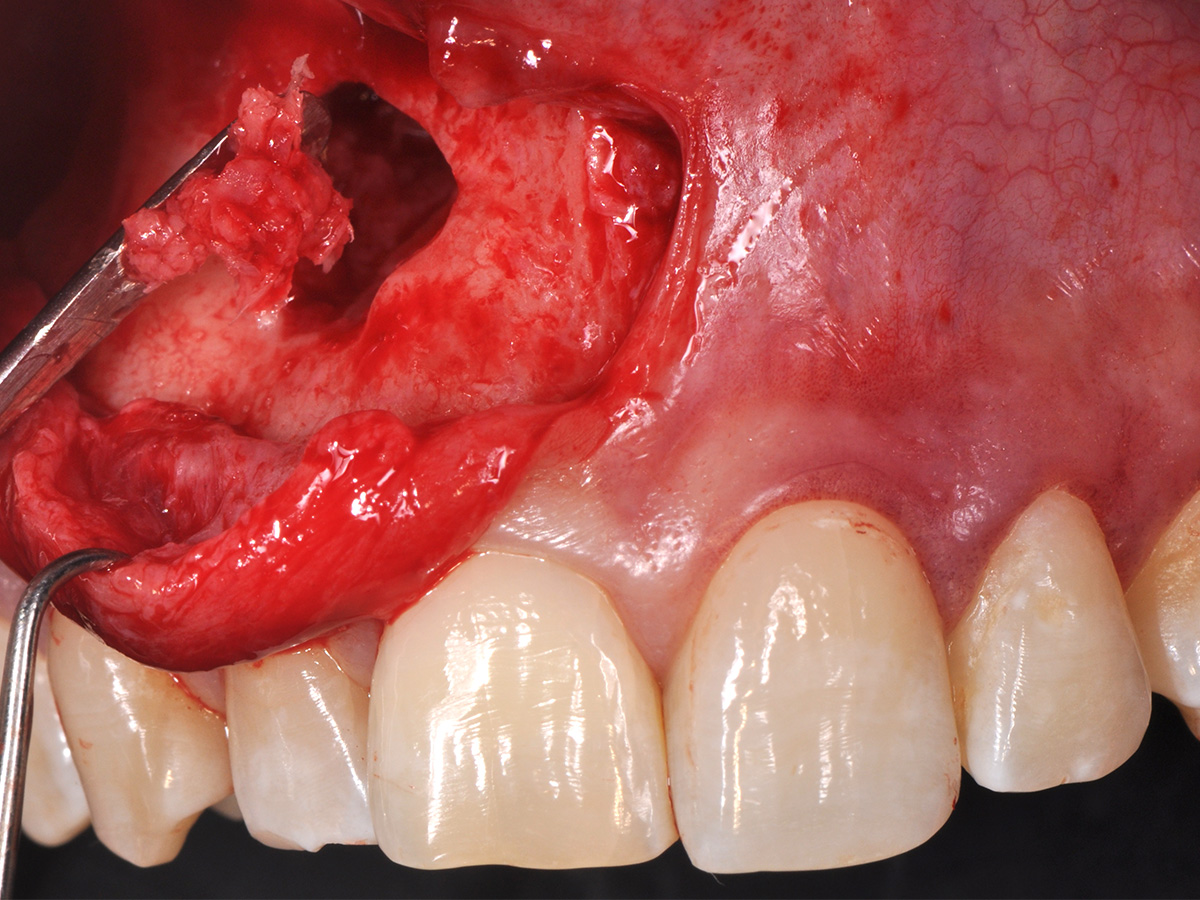

Abbildung 11

Anschließend erfolgte eine Wurzelspitzenresektion an den Zähnen 11 und 12 durch die vestibuläre ossäre Perforation, gefolgt von einer ultraschallbasierten, retrograden Kanalaufbereitung und Abdichtung mit MTA.

Mit der Patientin wurde der Versuch des Zahnerhaltes trotz ausgedehnter Zyste besprochen. Gleichzeitig sollte das Zystenlumen zu einer sicheren ossären Durchbauung geführt werden, um eine implantologische Sofortversorgung vorzubereiten, falls zu einem späteren Zeitpunkt eine Zahnentfernung notwendig werden sollte. In der Phase vor der geplanten Operation wurden die Wurzelkanalfüllungen an Zahn 11 und 12 durch einen Endodontologen alio loco revidiert. Die Schnittführung wurde aufgrund des bestehenden „Gummy Smile“ hoch im Vestibulum geführt – so konnte die delikate Parodontalstruktur in ihrer Form unangetastet belassen werden, um einen möglichst optimalen ästhetischen Erfolg zu erreichen (Abb. 8, 9). Nach vestibulärer Freilegung wurde die Zyste vollständig entfernt und zur histopathologischen Untersuchung eingesandt (Abb. 10). Anschließend erfolgte eine Wurzelspitzenresektion an den Zähnen 11 und 12 durch die vestibuläre ossäre Perforation (Abb. 11), gefolgt von einer ultraschallbasierten, retrograden Kanalaufbereitung und Abdichtung mit MTA. Um die knöcherne Durchbauung am Boden der Zyste osteoinduktiv zu unterstützen, wurden mit Hilfe eines mechanischen Knochenschabers aus dem Bereich des rechten naso-palatinalen Pfeilers Knochenchips entnommen und als erste basale Augmentationsschicht in den ossären Defekt eingebracht (Abb. 12). Der größere Anteil von 80 % des Defektvolumens wurde mit einem vollständig resorbierbaren, xenogenen Augmentationsmaterial aufgefüllt (Abb. 13) (mp3®, OsteoBiol®). Der Defekt wurde zum Vestibulum hin mit einer stabilen, vollständig degradierbaren Membran abgedeckt (Abb. 14) (Soft Cortical Lamina, OsteoBiol®). Zum einen wurde hiermit im Sinne der GBR das Weichgewebe vom Augmentat getrennt. Zum anderen verhinderte die stabile Membran das Einwachsen eines Weichgewebeankers in den Defekt und damit eine narbige Verziehung im Vestibulum. Um eine Verschiebung der Membran zu vermeiden, wurde diese mit zwei Titanpins in der Kortikalis fixiert. Die Pins wurden bei Beschwerdefreiheit in situ belassen (Titan-Bone-Pin-System). Der Wundverschluss erfolgte einschichtig mit nicht resorbierbarem Nahtmaterial (Abb. 15) (Seralene® 5-0 DS-15). Peri- und postoperativ wurde eine antibiotische Abschirmung unter Fortführung für insgesamt drei Tage mit Amoxiclav 875/125 1-0-1 durchgeführt.